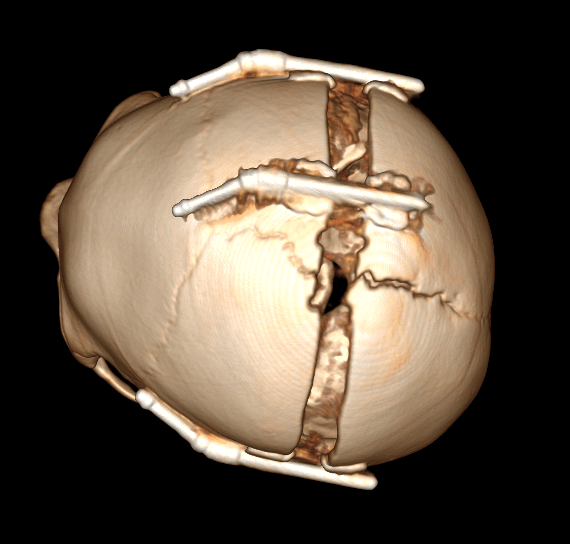

Брахиоцефалия – (от греч. brachy – короткий) возникает в следствии синостозирования коронарных швов с 2-х сторон. Характеризируется укорочением в передне-задних отделах и компенсаторным удлинением вверх в височных костях.

Метод лечения, также является хирургическим. При данной форме краниосиностоза используются дистракторы (выдвижная система), с помощью которых в течение 20-30 дней (ежедневно на 0,1-0,2мм) увеличивается объем черепа. По окончанию срока и удовлетворительному результату, данная система удаляется.

Рис. № 6 Брахиоцефалия

а) - до и после операции

б), в) - СКТ снимки после установки дистракторов.